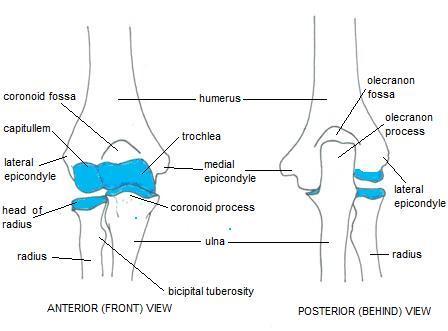

elbow humeral distal humerus

elbow radiology fractures radiography dislocations physiology schools

elbow anatomy paediatric wikiradiography pediatric ossification centres centers radiology medical injuries saved